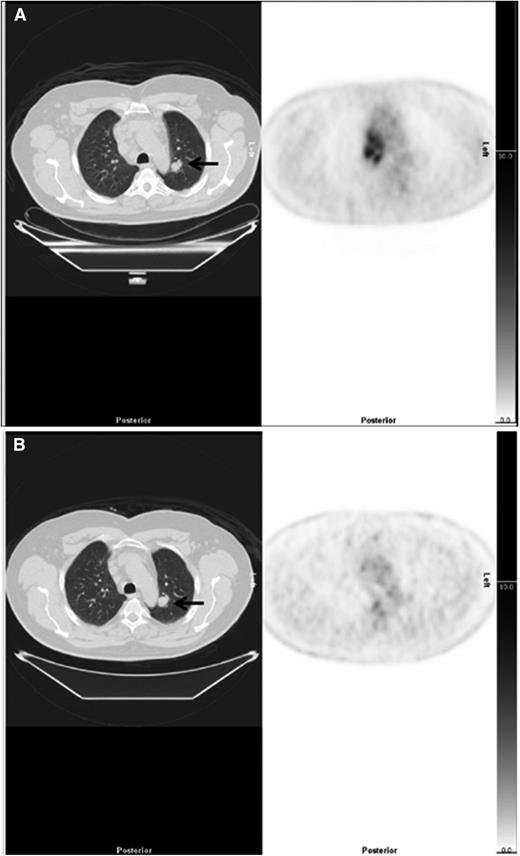

The PET2 scans of patients with discrepant staging findings were compared with the PET0 scan (supplemental Table 1, available on the Blood Web site). At PET2, FDG uptake at sites that resulted in upstaging decreased in parallel with other sites of disease during treatment in all cases (supplemental Table 1). Twenty patients had extranodal lesions on CT that were not FDG-avid. Five of these 20 patients had lesions that did not change on treatment (Figure 3) and were considered unlikely to represent lymphoma (1 adrenal adenoma, 3 lung nodule/s, 1 bone lesion). One patient had a 37-mm cavitating lung nodule on CT, which enlarged from 5-mm 7 days prior on PET-CT and was probably inflammatory. Six patients had indeterminate lung nodules, and 1 patient had lobar consolidation that all resolved; 3 patients had pleural effusions that resolved; in all these cases, the changes may have been reactive, inflammatory, or related to lymphoma. There were 4 patients, small bowel (1), liver lesions (2), and 1 patient with bowel and liver lesions, where ceCT was considered more likely to indicate the correct stage. Three patients had splenic lesions on ceCT not seen on PET. Bone marrow involvement was missed on PET-CT but identified on biopsy in 5 patients.

Example of downstaging by PET-CT. (Left) CT and (right) PET axial images show a case downstaged by PET-CT. (A) There was nodal disease in the mediastinum and a 22-mm lung nodule in the left lung (arrow), reported on CT as stage 4. The PET scan showed high uptake in lymph nodes but no FDG uptake in the lung nodule, suggesting the nodule was unlikely to be due to lymphoma interpreted as stage 2. (B) After treatment, there was resolution of uptake in lymph nodes but the lung nodule (arrow) was unchanged.